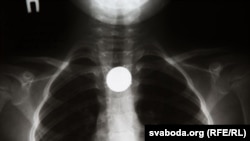

Так оно и оказалось. В первые две недели июля в хирургическом отделении Республиканского научного педиатрического центра (РНПЦ) наблюдался наплыв: иногда туда поступало более десяти маленьких пациентов за день. В некоторых случаях процедура по извлечению монет проводится под наркозом. Для этого используется эндоскоп, который вводят в ротовую полость ребенка, чтобы достать монету из желудка или верхней части тонкой кишки.

Заведующий отделением детской хирургии РНПЦ Александр Свирский сообщил Белорусской редакции Азаттыка, что к ним поступают в основном дети в возрасте от двух до пяти лет: